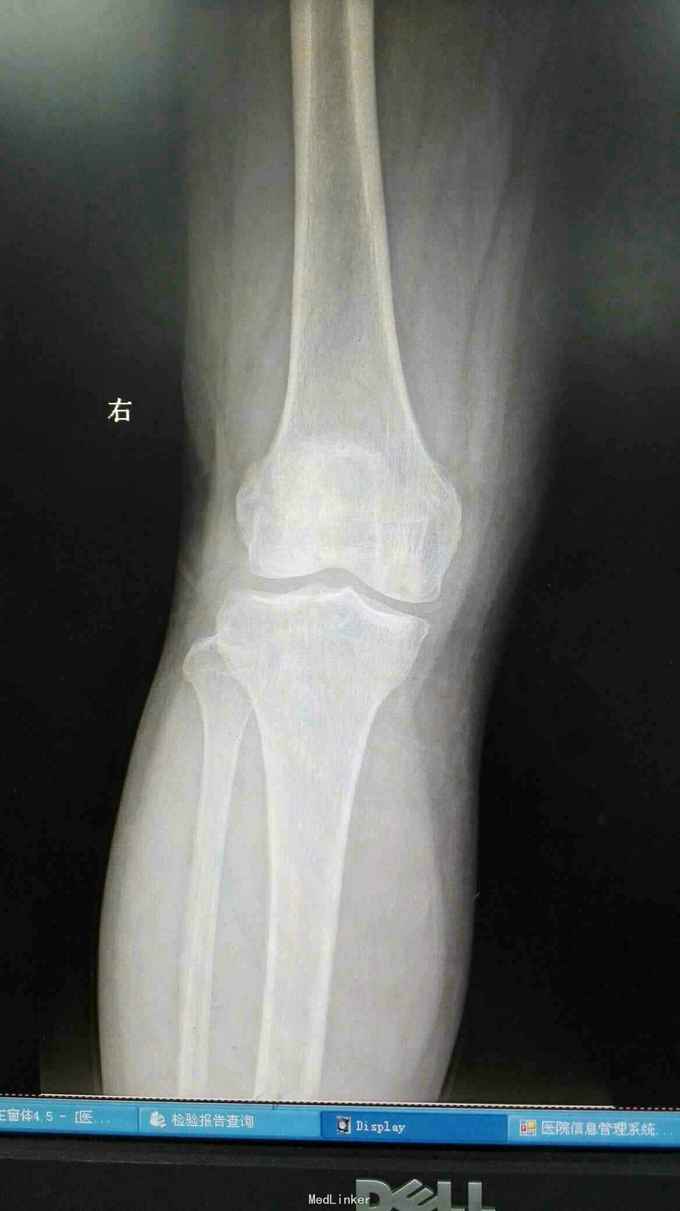

右膝外形正常,皮温正常,右膝内前方压痛(+),前后抽屉试验(-),侧方应力试验(-)、研磨试验内侧(+),关节活动度正常,左膝正常。 站立位膝关节正侧位片提示:右膝关节轻度退行性变,内侧关节间隙稍变窄 右膝关节MRI提示:右股骨内侧髁水肿,考虑局部骨坏死 实验室检查:各炎症指标均正常

诊断:1、右股骨内侧髁骨坏死 2、右膝关节骨性关节炎 治疗:行右膝关节单髁置换术